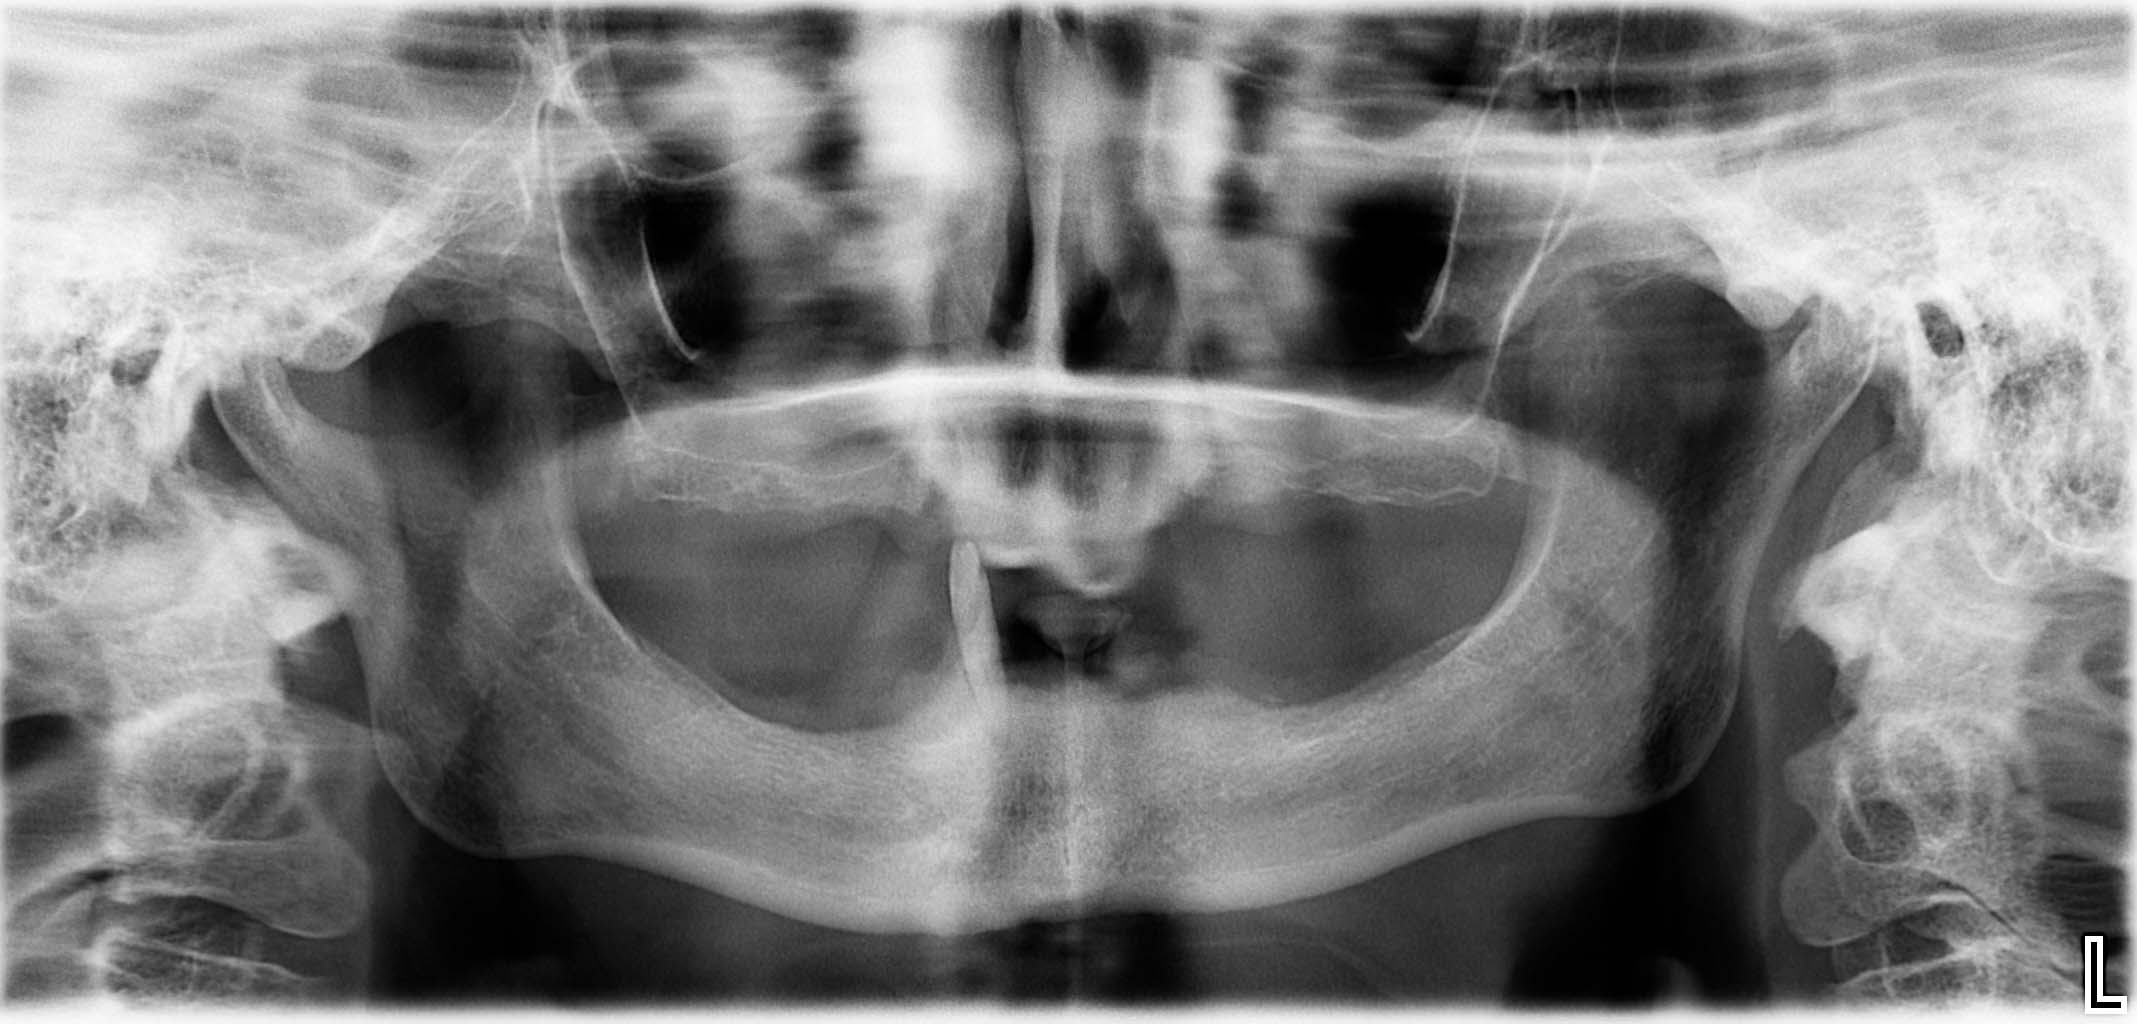

Erfolgreich implantierte Patientenfälle (klinische Fotos)